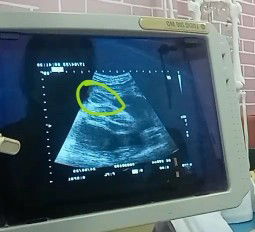

แม่ๆคิดว่าลูกสาว หรือ ลูกชายค่ะ

อันนี้ใช่เพศหญิงมั้ยค่ะพอดีคุนหมอบอก เพศหญิง90%ค่ะ เพราะว่าอยากได้ลูกสาวยุแล้ว คนแรกได้ลูกชายค่ะ#ขอบคุณล่วงหน้านะคะ #ขอคำแนะนำหน่อยค่ะ #ขอบคุณสำหรับคำตอบค่ะ

แม่ๆได้เพศหญิงหรือชายค่ะ

ขอดูใบอัลตร้าซาวด์ของแม่ๆหน่อยค่ะ ว่าเพศ หญิง หรือ ชายค่ะ บ้านนี้หมอบอกได้ลูกสาว แต่ไม่แน่ใจค่ะ แม่ๆดูให้หน่อยค่ะชายหรือหญิงค่ะ#ขอบคุณล่วงหน้านะคะ #ขอคำแนะนำหน่อยค่ะ #ขอบคุณสำหรับคำตอบค่ะ